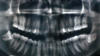

what is the angulation of the lower left and right third molars

lower left = horizontally impacted lower right = mesially impacted

47

lower left = distally impacted lower right = horizontally impacted

48

lower left = distal impaction (angled backwards towards ramus) lower right = true vertical impaction (following same course as 7, coming into length of curve of spee)